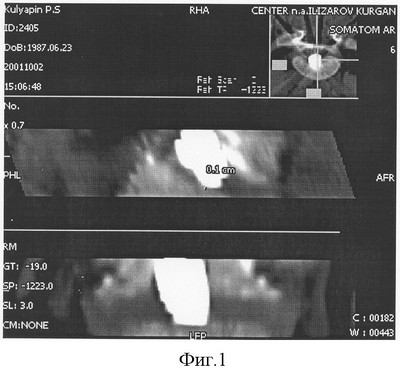

В послеоперационном периоде регулярно осуществлялся рентгеноконтроль зоны спондилодеза, в том числе с помощью компьютерной томографии. При выполнении последней сканирование производили по линии, проходящей не далее чем 0,5 см от зоны соприкосновения торцов имплантата с поверхностью тел L5 и S1 позвонков. Одновременно по указанным линиям сканирования определяли коэффициент ослабления рентгеновского излучения и наличие участков резорбции.

Так, при выполнении компьютерной томографии, на 30 день фиксации коэффициент ослабления рентгеновского излучения по линии, проходящей не далее чем 0,5 см от зоны соприкосновения торца трансплантата с телом L5 позвонка составил 100 HU и с телом S1 позвонка – 150 HU. Это указывало на незавершенность спондилодеза и, фиксация позвоночного столба была продолжена.

При выполнении компьютерной томографии на 60 день фиксации показатели коэффициента ослабления рентгеновского излучения по линии, проходящей не далее чем 0,5 см от зоны соприкосновения трансплантата с телом L5 позвонка составили 340 HU, а с телом S1 позвонка 320 HU. Одновременное отсутствие участков резорбции костной ткани послужило основанием для демонтажа аппарата наружной фиксации.